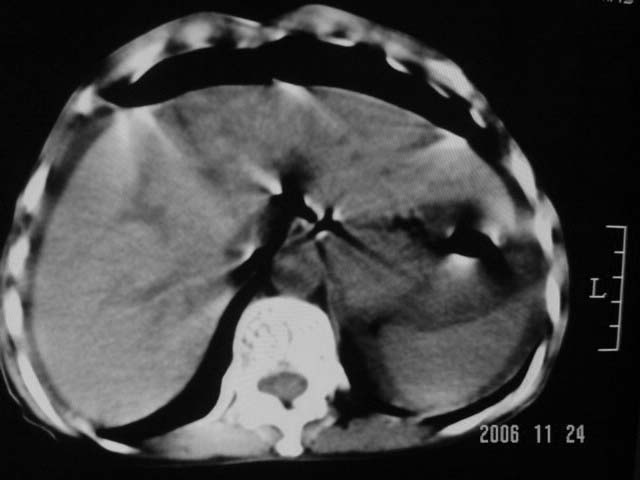

仰卧位见:肝前间隙及肝脾间隙内可见新月形气体密度影,边缘清楚,侧卧位见气体随体位改变而移动,ct值约-929hu。膈下、肝下间隙及部分肠间隙可见液性密度影。考虑:1、上腹部空腔脏器穿孔,以胃穿孔可能性大。2、少量腹水。

仰卧位见:肝前间隙及肝脾间隙内可见新月形气体密度影,边缘清楚,侧卧位见气体随体位改变而移动,ct值约-929hu。膈下、肝下间隙及部分肠间隙可见液性密度影。考虑:1、上腹部空腔脏器穿孔,结合临床,首先考虑胃穿孔可能性大。2、少量腹水

补充--肝门及肝肾间隙以见积气显示。

支持消化道空腔脏器穿孔(腹腔内大量游离气体影,小网膜囊内亦见气体影),少量腹水。